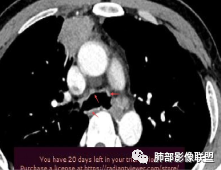

肝脏病变明确,是轻度强化,延迟强化特点,边缘模糊,有轻微的包膜挛缩。

6